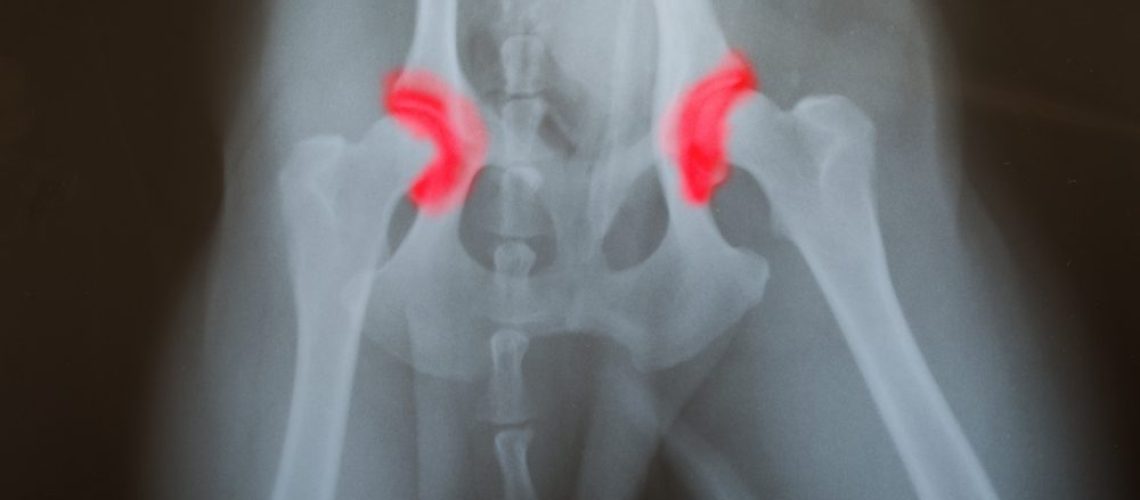

A displasia do desenvolvimento do quadril (DDQ) ou luxação congênita, como é conhecida, é uma enfermidade que afeta aos recém-nascidos e ocasionada por uma má formação das estruturas ósseas.

Ela se caracteriza pela perda do contato da cabeça do fêmur com o acetábulo durante o parto do bebê. Essa má formação prejudica a estabilidade das articulações e pode parecer que o quadril do indivíduo está “solto” (displásico).